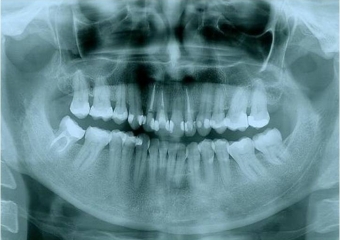

Raio x inicial com presença de lesão periapical no incisivo lateral superior esquerdo - Clínica Cliniface

Raio x inicial com presença de lesão periapical no incisivo lateral superior esquerdo